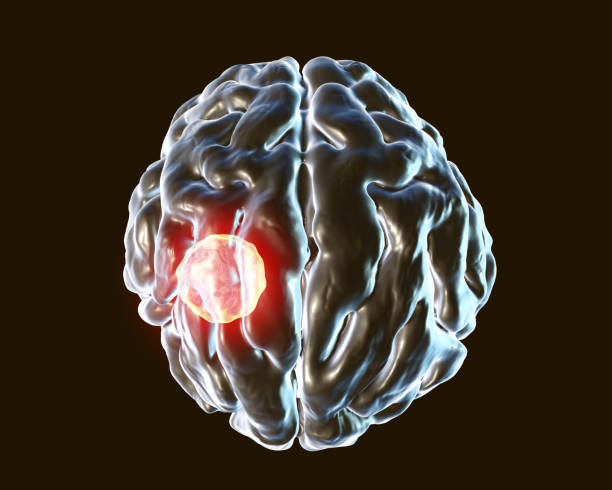

✅뇌경색 후유증 종류

뇌경색 후유증은 다양한 증상을 유발할 수 있습니다. 이러한 증상은 흔히 다음과 같이 나눌 수 있습니다.

1. 전두엽 손상

뇌경색 후, 이마 부위에 손상이 생기면 하체의 힘이 약해질 수 있습니다. 이로 인해 환자는 걷거나 움직일 때 한 쪽으로 기울거나 반쪽의 마비가 발생할 수 있습니다. 대소변의 장애, 성격 변화, 사고력 저하, 집중력 감소 등과 같은 부작용도 나타날 수 있습니다.